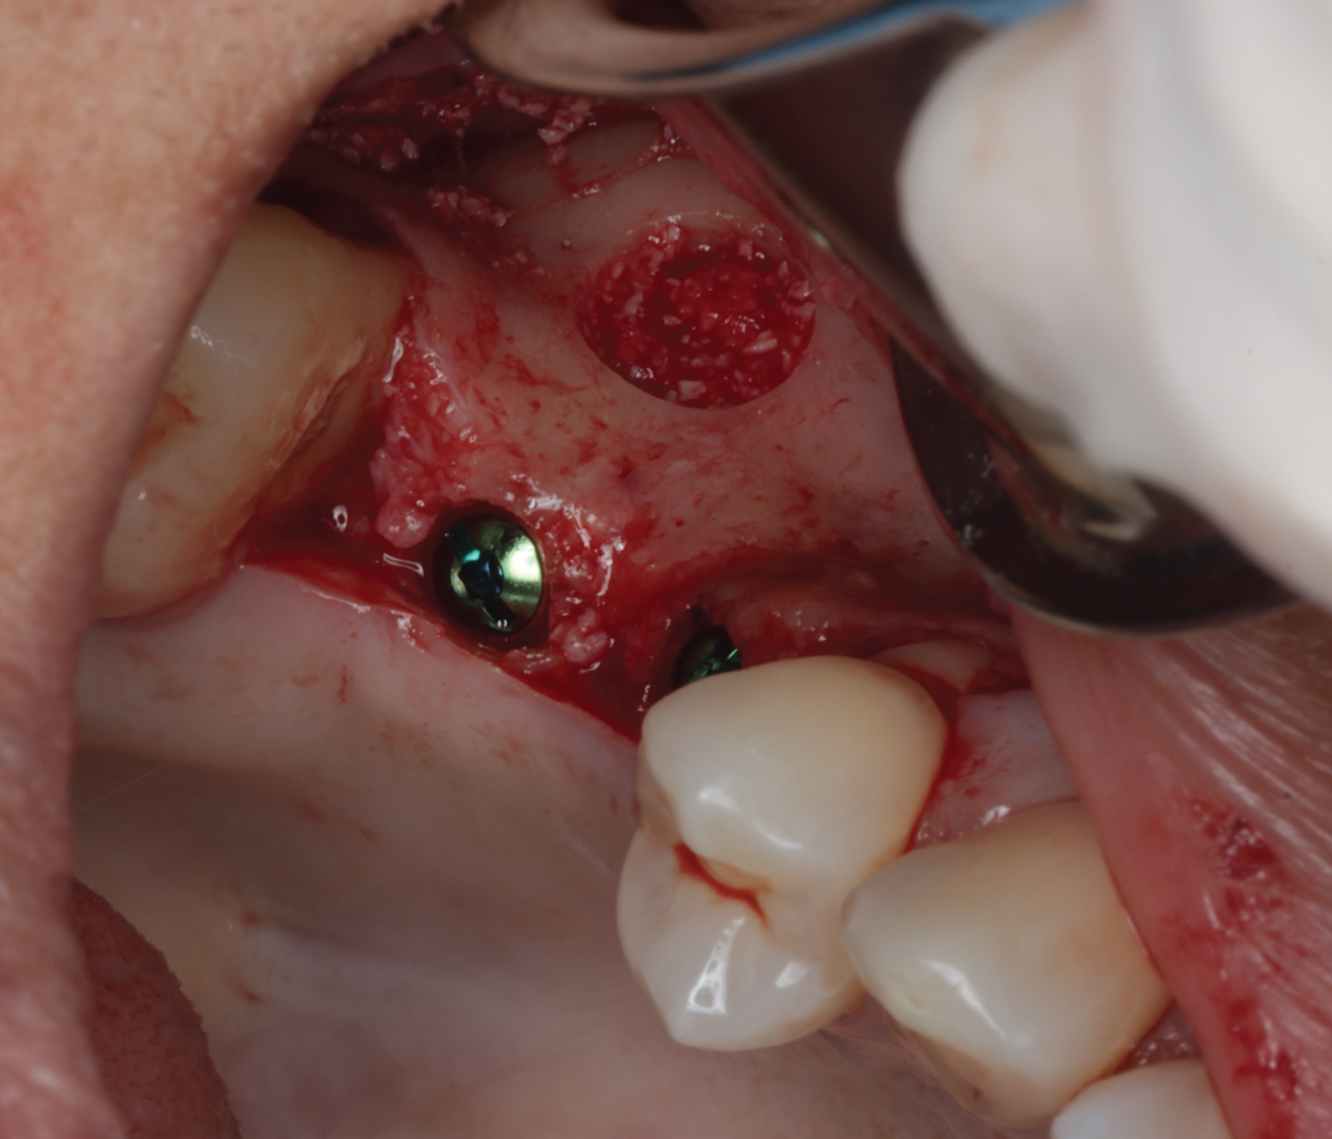

Director’s Clinical Cases

Director’s Clinical Cases